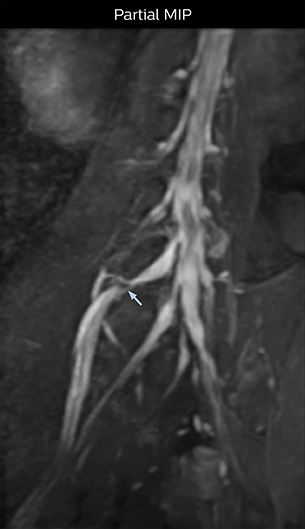

At Northern Fukushima Medical Center in Japan, excellent MRI visualization of nerves helps support confident diagnoses and informs surgical treatment decisions for patients with lower limb symptoms. MRI technologist Tanji and orthopedic surgeon Dr. Yabuki share how direct nerve visualization with the 3D NerveVIEW method adds information when diagnosing atypical herniations. The additional insights changed their way of working and benefit their patient care, as illustrated by some clinical examples.

“In patients with lower extremity neurological symptoms, NerveVIEW helps us to determine the disease matching the patient’s symptoms by directly visualizing the nerves. We use the sequence mainly, when there is suspicion of intraforaminal stenosis, extraforaminal stenosis or lateral disc herniation, which is often based on routine T2- and T1-weighted images. Additionally, the excellent depiction of the course of nerves makes NerveVIEW a good navigator when applying treatment such as block therapy or surgery.”

“In such case, we would then browse through axial T2-weighted MR images slice by slice and mentally reconstruct the actual situation based on both radiculography and MRI. Fortunately, NerveVIEW can now very well show nerve courses and presence of nerve compression or edema in one single image series.” “We have often seen NerveVIEW directly depict details of the nerve compression that were not observed by radiculography. Therefore, we think that with NerveVIEW we can reduce the number of invasive examinations, especially for some patients with lumbar plexus symptoms.”

The key concept in MR neurography, Dr. Yabuki stresses, is the ability to directly visualize spinal nerves, versus inferring the presence of pathology indirectly. “Before NerveVIEW, we estimated compression of the nerve by looking for the presence or absence of fat signal on other MR images,” he says.

“For example, in sagittal images, when the presence of fat is observed in the intervertebral foramen, it suggests that there is a margin around the nerve. Similarly, the absence of fat indicates that the nerve is being compressed. So, we used to deduce nerve compression indirectly. With NerveVIEW, however, we can observe the condition of the nerves directly, regardless of the presence or absence of fat. We always prefer such direct observation of anatomy over having to make an inference about it.”

“Although symptoms of typical disc herniation and atypical hernia are very similar, the actual site of herniation is different. It is therefore important to characterize the nerve’s condition both inside and outside of the intervertebral foramina. “Conversely, if we see no abnormality in NerveVIEW, we can assume at least that there is no severe condition that requires surgery. Like this, it can help us avoid unnecessary surgery. NerveVIEW can have a tremendous impact in this way.”

“NerveVIEW is really useful for those cases where a nerve disorder is strongly suspected based on the clinical examination but our regular MRI images do not show any findings. These atypical herniations and spinal canal stenosis, occurring in 5% to 15% of the total lumbar herniation/stenosis cases are our main target when using NerveVIEW,” says Dr. Yabuki.